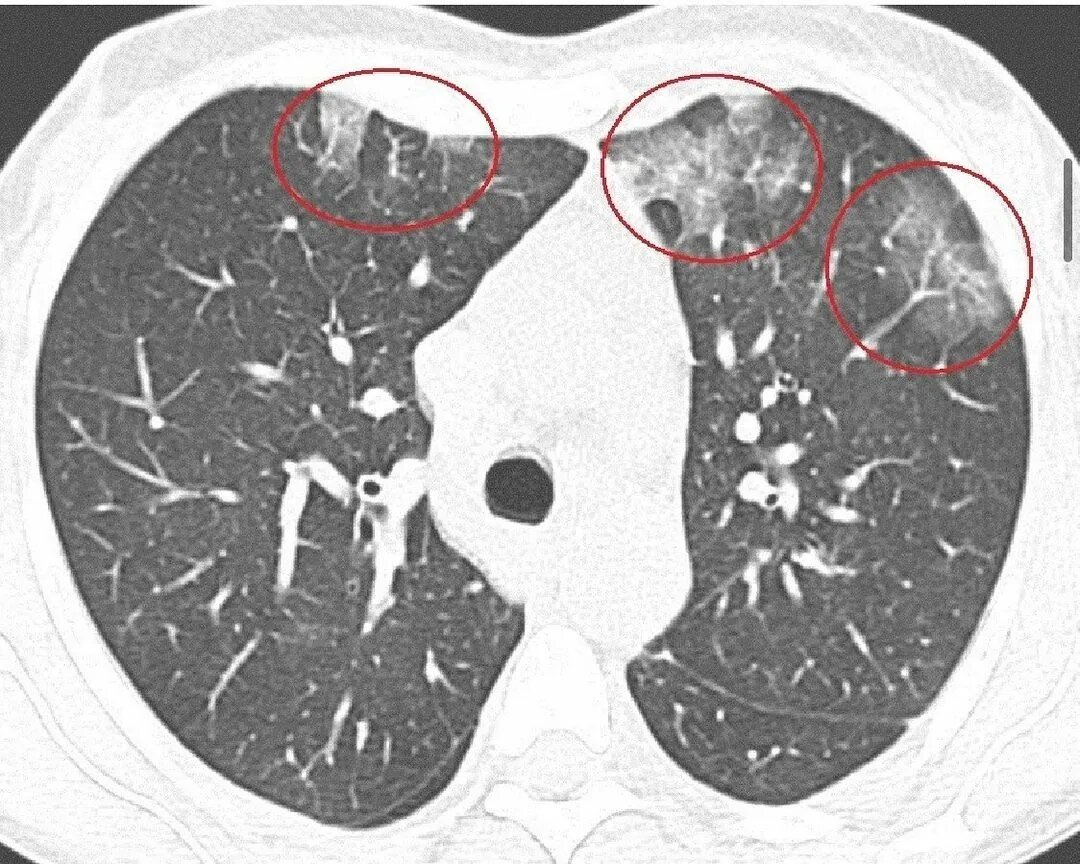

Болезнь эта возникает у пациентов, употребляющих вейп, причём патогенез её изучен далеко не полностью. Предполагают, что накопление в лёгочной ткани масляных компонентов от вейпов (а жидкости для них содержат, например, ацетат жирорастворимого витамина Е) приводит к образованию очагов в лёгких по типу матового стекла. Именно сходные по виду очаги образуются при пневмонии, осложнившей новую вирусную инфекцию. Так вот, поражение лёгких с формированием таких очагов может вызвать тяжёлую дыхательную недостаточность. Бороться с этой болезнью пока не научились. Есть данные, что отказ от употребления вейпов может улучшить состояние пациентов, но это бывает не всегда. Зафиксированы летальные исходы на фоне этого заболевания, правда, в некоторых случаях помогает введение стероидных гормонов.

Именно так выглядит пресловутое "матовое стекло", о котором, наверное, слышали практически все.

Недавно я был участником конференции, на которой был доложен необычный случай. Молодой пациент поступил в пульмонологическое отделение крупного многопрофильного стационара. Он жаловался на одышку, сухой кашель, боль в груди при глубоком дыхании. Было высказано предположение о пневмонии, но всё же, течение заболевания не было похоже на классическую картину этого заболевания. Тем более, температура тела оставалась нормальной, а в анализах крови не было типичных для инфекционного процесса изменений. Была назначена компьютерная томография органов грудной клетки, которая выявила множественные крупные очаги по типу «матового стекла».